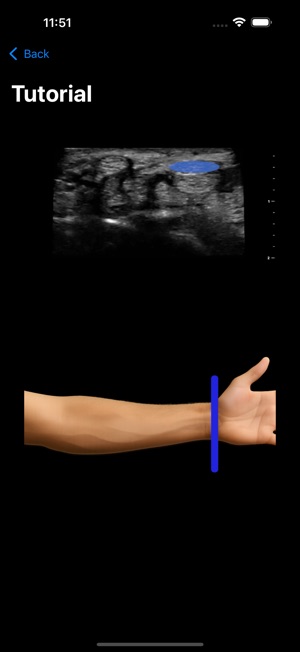

MSK VUE is a specialized training application for musculoskeletal ultrasound. The system utilizes an artificial intelligence component to support the identification of key peripheral anatomical structures within an interactive, simulated ultrasound imaging environment. The interface is designed to present visualizations of nerves, tendons, and bones, allowing users to engage with the simulated data. This application's core mechanism focuses on presenting specific anatomical targets and facilitating their recognition through its AI-driven framework, providing a platform for practice in a non-clinical context.

This application is designed for clinicians seeking to develop proficiency in musculoskeletal ultrasound. It functions as a supplementary educational tool for practicing the identification of peripheral anatomical structures within a simulated environment. This app is intended for educational purposes and does not replace professional medical advice, diagnosis, or treatment; the provided description explicitly prohibits its use in any clinical setting or for any clinical purposes.